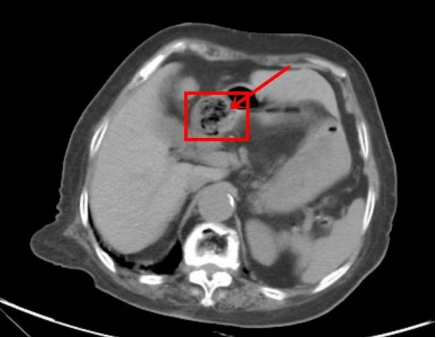

如果您最近吃了大量的柿子、山楂、黑枣、石榴等,又出现上述症状,请前往正规医院行钡餐、 CT 或胃镜检查。

腹部CT检查